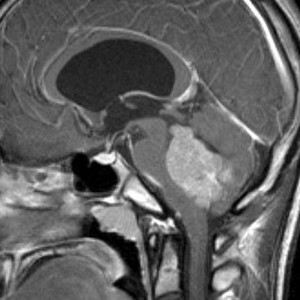

毛様細胞性星細胞腫 pilocytic astrocytoma

毛様細胞性星細胞腫です。左のガドリニウム増強T1像では髄芽腫と区別できませんが,真ん中のCISSの画像で低信号,右のT2強調画像で強い高信号になるのが特徴です。最上部に小さなのう胞が2つあります。